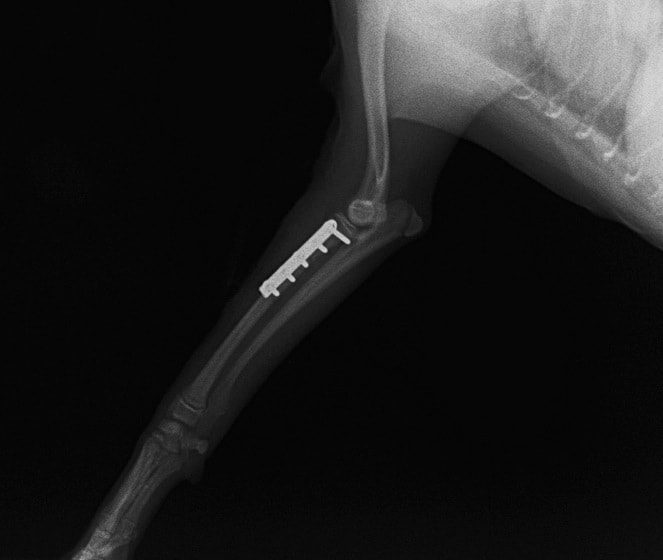

ペルシャ猫 11ヶ月齢 雄

他院にて左大腿骨遠位の成長板骨折(salter-harrisⅠ型)が認められており、治療相談を目的として来院。当院にて、キルシュナーワイヤーを用いたピンニングにより骨折部位の整復を行いました。術後の経過は良好で、現在も経過観察中です。

術後レントゲン

Arthrex社のターゲティングデバイスを用いてピンニングの位置を調整することで、確実な固定を行っています。当院ではこの手術器具以外にも、人の手術にも使用される様々な器具を導入し、手術精度を高め、また医療メーカーと新しい器具の開発、試作にも取り組んでおります。